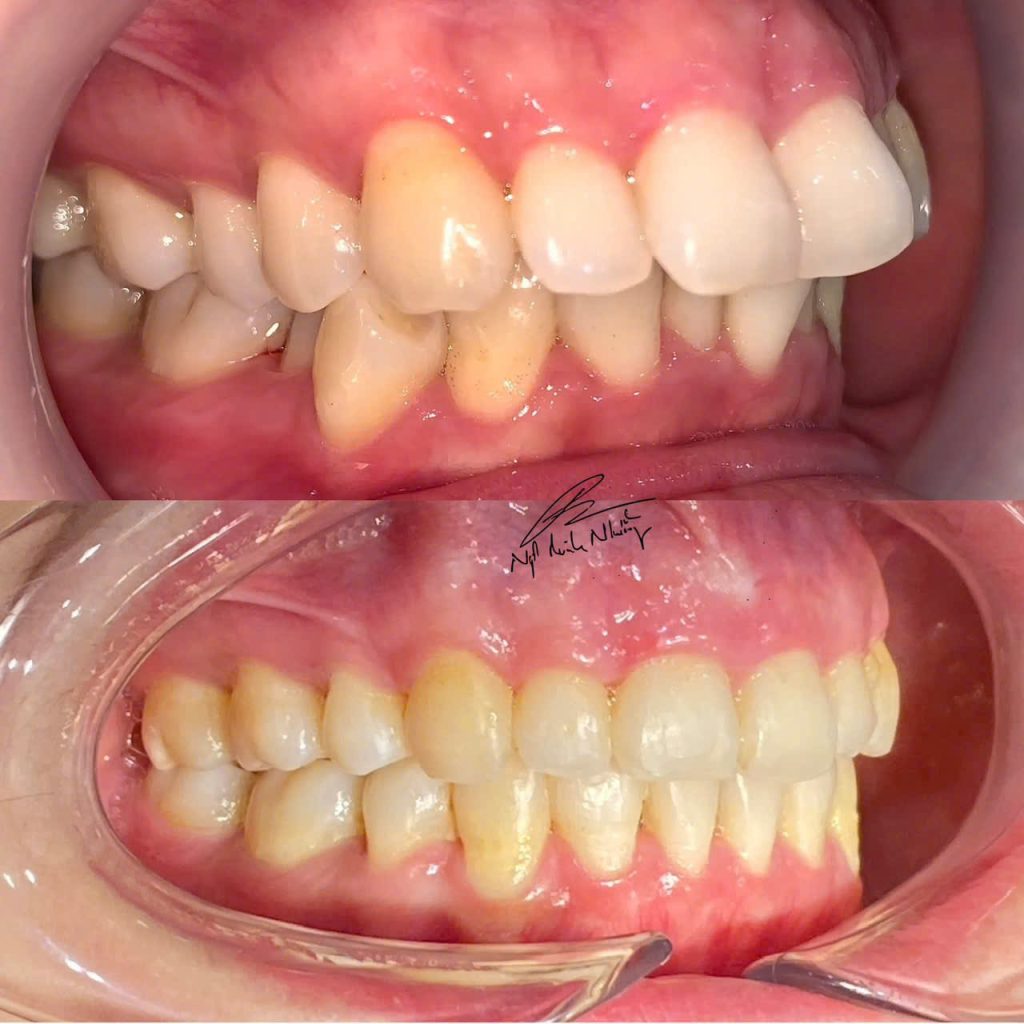

Một ca tiếp theo thay đổi E line, tương quan mũi-môi-cằm nhờ niềng răng: